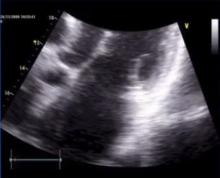

Approach to Functional Mitral Regurgitation [1]

Hans-Joachim Schaefers of Saarland University Medical Center, Homburg/Saar, Germany, discusses the pathophysiology of functional mitral regurgitation. Dr. Schaefers stresses the importance of addressing the ventricular component of the disease to achieve a durable repair.